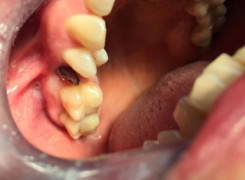

Pan Ryszard trafił do Naszego Gabinetu z jasno sprecyzowanym oczekiwaniem. Miał 84 lata i chciał odzyskać możliwość swobodnego spożywania posiłków oraz poprawienia sobie komfortu życia a także prosił aby przywrócić mu piękny uśmiech jakim cieszył się przed laty. Już na początku pierwszej rozmowy zastrzegł, że interesuje go wyłączenie rozwiązanie uzupełnieniem protetycznym stałym. Nie miał zamiaru użytkować żadnych protez ruchomych. Mając na uwadze powyższe wykonaliśmy Panu Ryszardowi zdjęcie pantomograficzne oraz badanie tomograficzne szczęki i żuchwy na postawie których zapanowywaliśmy Pacjentowi optymalne rozwiązanie – stałe uzupełnienie protetyczne w postaci 28 koron cyrkonowych zamontowanych do dwóch belek cyrkonowych które będą przymocowane do 16 implantów w konfiguracji 8 wszczepów w szczęcie 8 w żuchwie. Po omówieniu powyższego planu przystąpiliśmy do Wspólnej pracy której efekty w poszczególnych etapach prezentujemy poniżej.